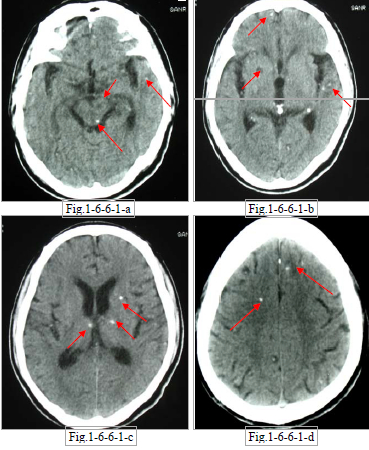

由猪肉绦虫的幼虫(囊尾蚴)寄生在人脑内而引起的病变,常发生在大脑皮质运动区,因癫痫反复发作就诊。也可寄生在小脑、脑室及其他脑组织。后期可发生钙化。

患者男性,59 岁。主诉:间断右上肢抽搐 14 年。 CT 平扫(Fig.1-6-6-1-a~d)示:脑囊虫病,大部钙化;并有脑萎缩及右豆状核、脑干腔梗。